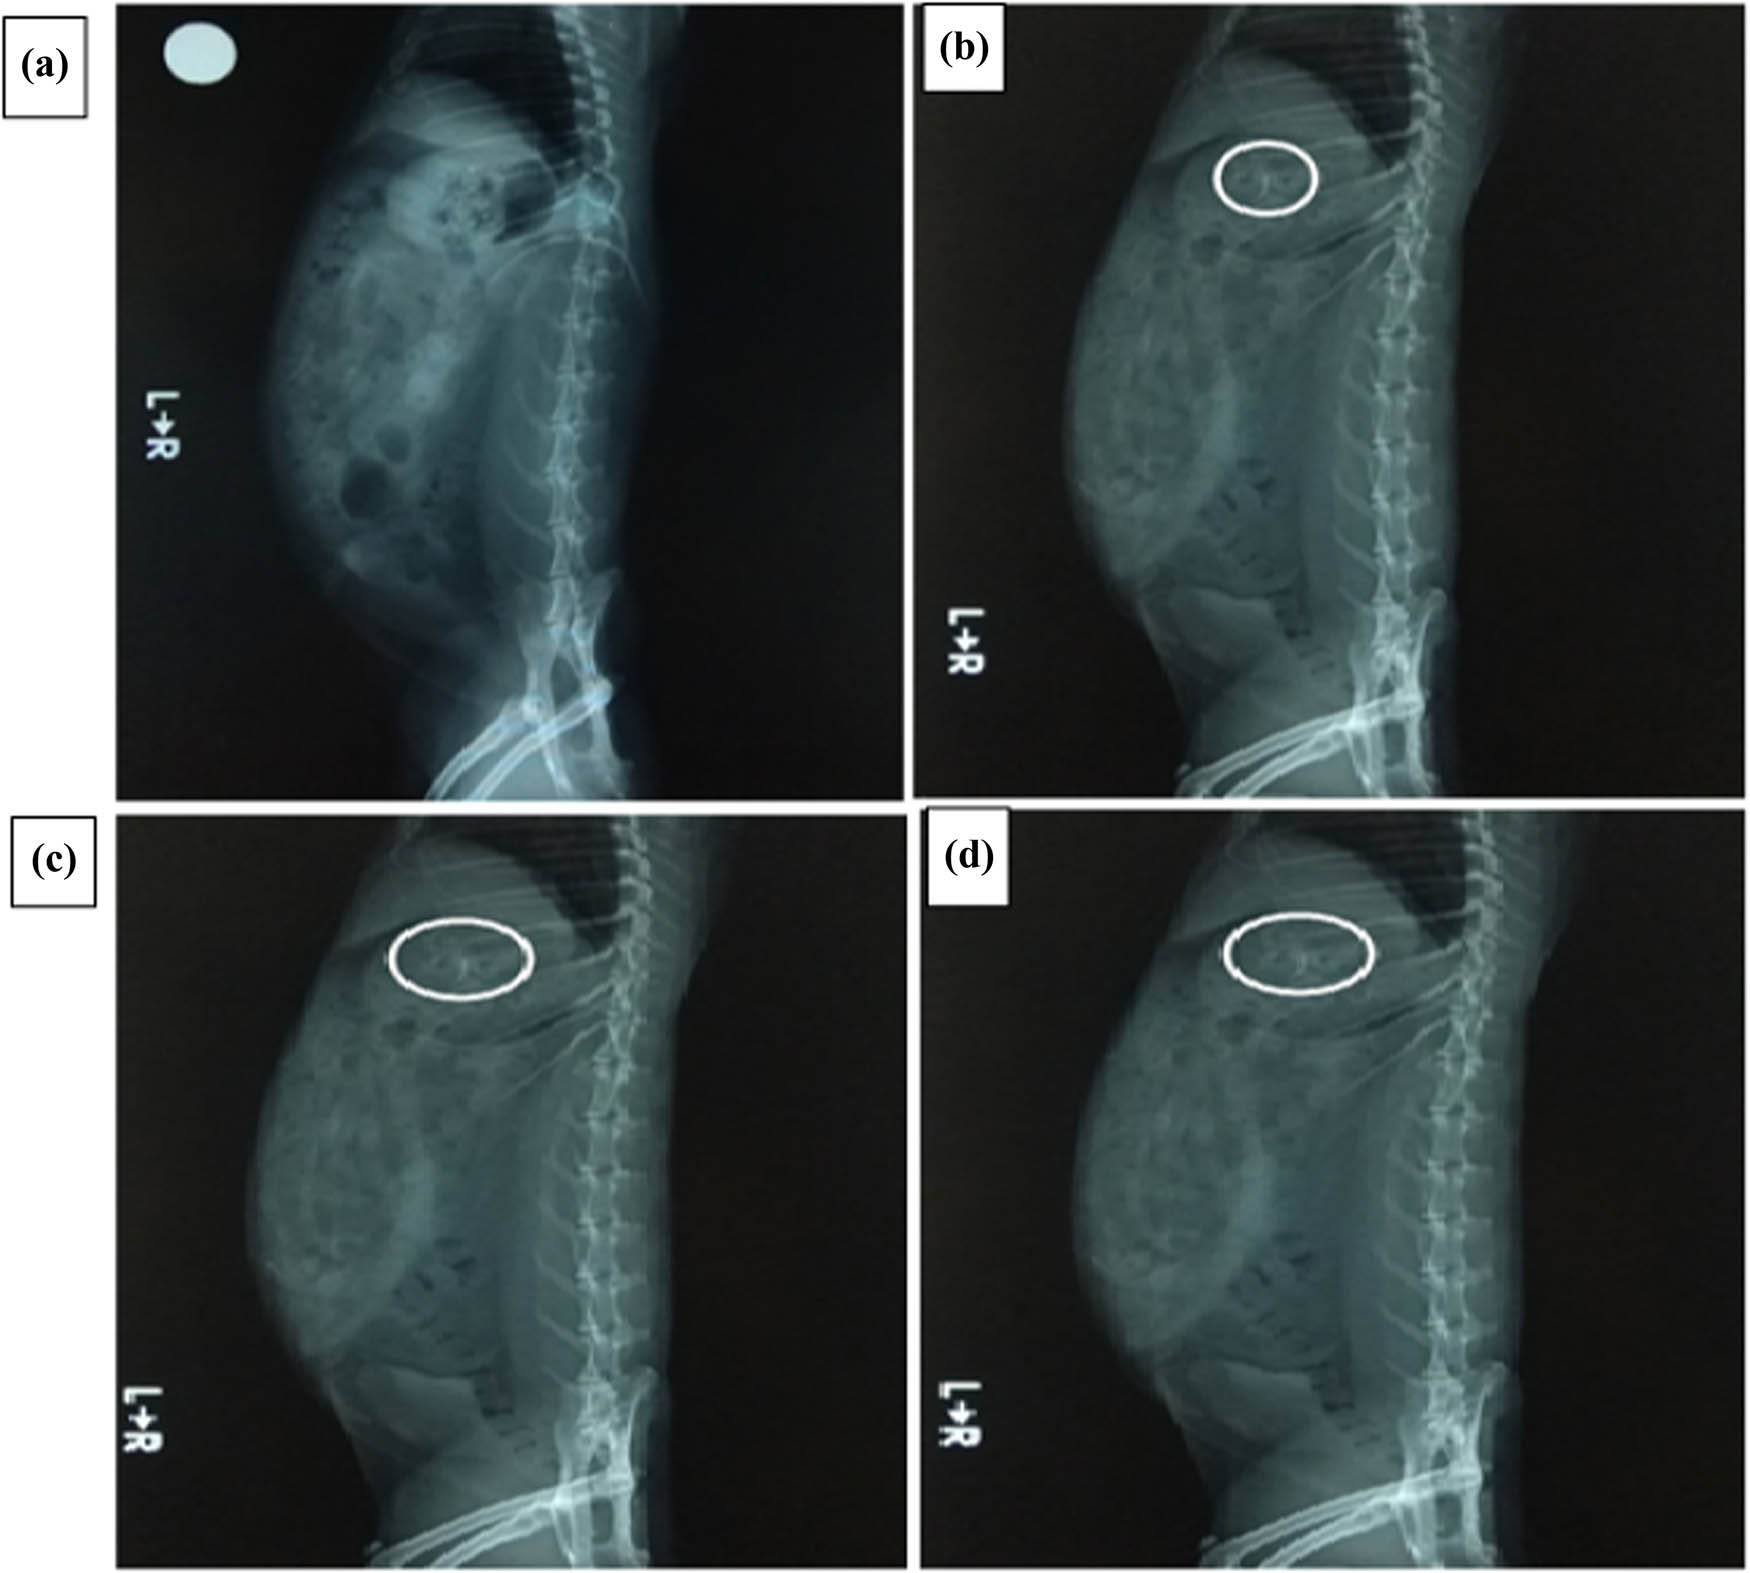

2.3.10 In vivo X-ray imaging studies

The representative images of the in vivo radiographic studies (33) with the bilayer floating tablets are captured in Figure 5. The in vivo studies revealed that the mean gastric retention time for the tablets from the optimized batch correlated well with the in vitro floating time. The studies indicated that the bilayer floating tablets from the optimized batch remained in the stomach for a mean period of 5.5 ± 1.0 h in rabbits which was significantly higher (p < 0.05) than the conventional tablets that displayed a mean gastric retention time of less than 2 h. The bilayer tablets by virtue of the floating properties were found to be well-retained in the stomach, despite the action of peristalsis and forcible housekeeping waves compared to the conventional tablets. As the tablets are well-retained in the stomach proximal to the absorption window and probably release the contents in a controlled manner, they are less likely to saturate the calcium transporters situated in the duodenal region of the gastrointestinal tract and therefore may exhibit a superior bioavailability compared to the conventional tablets.

Radiographic images portraying the bilayer floating tablet containing barium sulfate as a radio opaque marker in the stomach of rabbits at 0 h (a), 2 h (b), 4 h (c), and 6 h (d); the tablet is pointed by a circle.